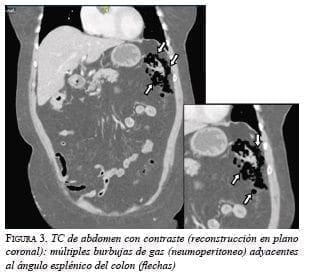

En las tres pacientes, la TC abdominal con contraste mostró el neumoperitoneo pericólico o localizado a menos de 5 cm del asa inflamada sin aire distante (figuras 2 y 3); dos presentaron divertículos en el ángulo esplénico, colon descendente y sigmoide, y una en el colon sigmoide únicamente.

La diverticulitis en las tres pacientes fue de grado Ia por la presencia de inflamación pericólica y la clasificación de Hinchey modificada por Wasvary, y grave por la presencia de aire externo a la luz intestinal en la TC y la clasificación de Ambrosetti (tabla 1) 5.